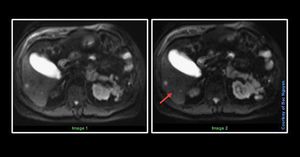

Liver Diffusion Weighed Imaging – Optimalization @ Siemens Nowadays, DWI is widely used outside the brain. It’s a powerful diagnostic tool. When it comes to liver imaging, its usefulness would be detection. Why not characterization? Due to focal liver lesions, the ADC values varies both from benign and malign, this means some lesions which is benign could have low ADC, and vice versa. In the combination of t1w and t2w, DWI and contrast agent (hepatobiliary gadolinium) most liver lesions can be adequately diagnosed. I want to highlight a parameter which can improve the liver detection with DWI. Differences between image 1 and image 2 are only one parameter change. Look closely at the liver parenchyma, image 2 has a darker liver parenchyma which can be more helpful to distinguish between liver and lesions. I will reveal this later, so people get the chance to run their mind :) #Siemens_MRI #siemens #mri #liver_imaging #dwi #optimising